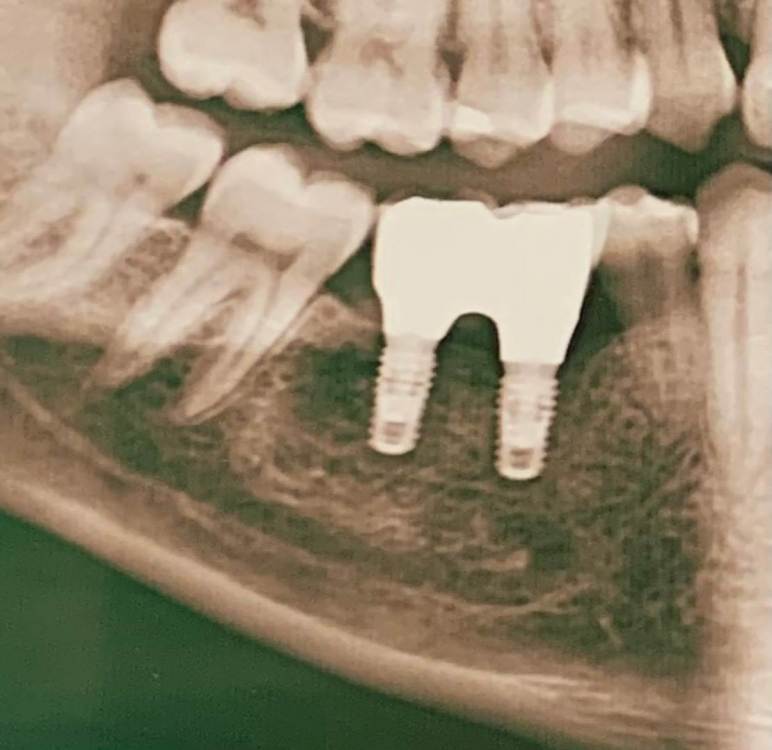

Периимплантит или нет ?

Здравствуйте! Шесть месяцев назад поставили коронки на импланты. Вторую неделю чувствую ноющую боль в области имплантов. Никаких выделений не наблюдаю, конструкция неподвижна. В чем может быть проблема ? Лечащий врач в отпуске..

IMG_1324.jpeg